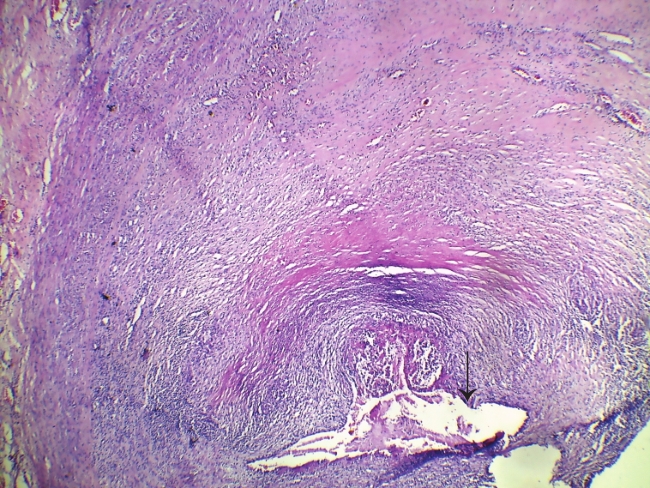

孤立性主动脉窦粥样硬化斑块致冠状动脉开口狭窄猝死1例

Sudden Death Due to Coronary Artery Stenosis Caused by Isolated Atherosclerotic Plaque of Aortic Sinus: A Case Report

关键词: 法医病理学, 猝死, 冠状动脉开口狭窄, 主动脉窦, 粥样硬化